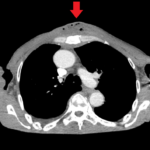

This case report highlights an uncommon sequelae of chest wall trauma that should be evaluated for patients presenting with similar history and symptoms. A 60-year-old man presented to the emergency department (ED) with swelling, fever, and chest wall pain two days after an assault with blunt chest wall trauma. On exam, there was a suspected chest wall abscess, verified on computed tomography (CT) with associated displaced midsternal fracture. This patient was admitted for abscess incision and drainage. While uncommon, chest wall abscess formation is an important condition that should be considered as a differential diagnosis in any patient presenting with chest wall pain post blunt trauma. With few reported similar presentations in the literature, this case is an important addition in a likely underreported phenomenon that requires prompt evaluation and treatment.